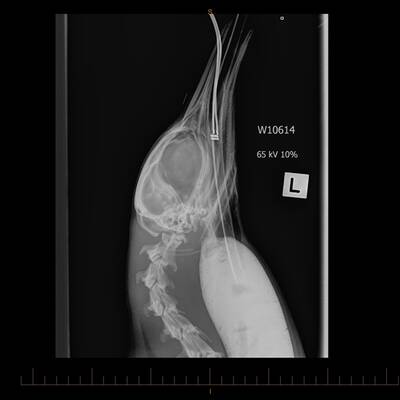

Der Sand bekam dem Kaiserpinguin aber gar nicht , sein Magen musste mehrfach im Zoo von Wellington ausgespült werden.

Die Neuseeländer nannten das Tier „Happy Feet“ , nach einem Pinguin aus einem Trickfilm. Zuerst sah es nicht gut aus für „Happy Feet“, er musste sogar ins künstliche Koma geschickt werden. Aber das Tier er­holte sich überraschend schnell, als der Magen von Sand und Treibholz befreit war. Rund 30 Deka Mist wurde entfernt. Dann war der Vogel wieder forsch.